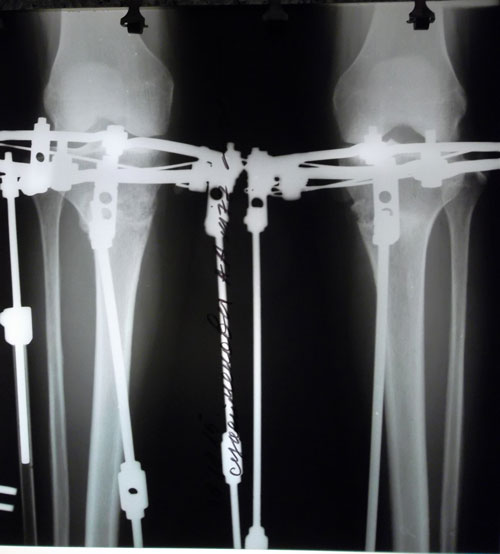

рентген в 90 дней.

пора на снятие аппаратов!

Рентген в день снятия аппаратов.

Вложения

Дата операции 28.07.2015г.

Дата снятия аппаратов 30.10.2015г.

Срок лечения 92 дня.

Высылаю фото рентген за 20.12.15 через 1,5 мес после снятия аппаратов